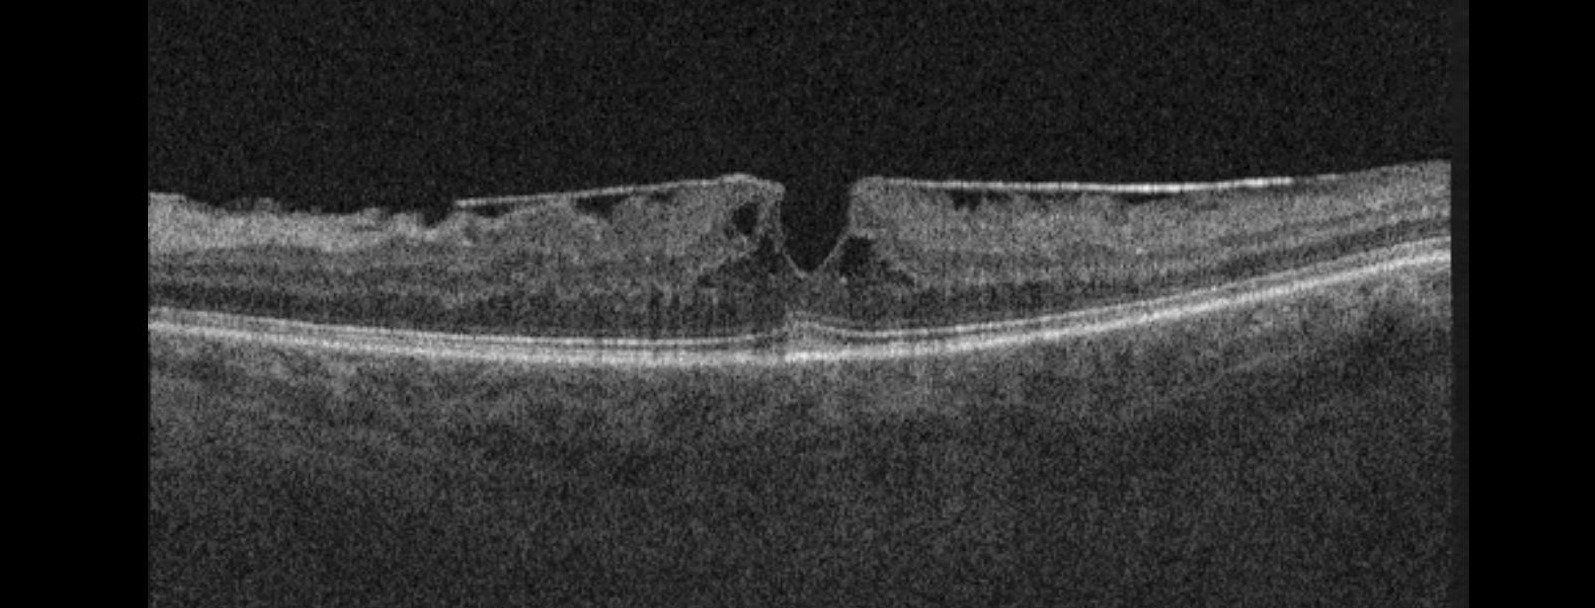

Best's Disease -

This is a genetic condition caused by the inability of the cells at the macula to regenerate properly. The result is a buildup of yellow pigment at the macula.